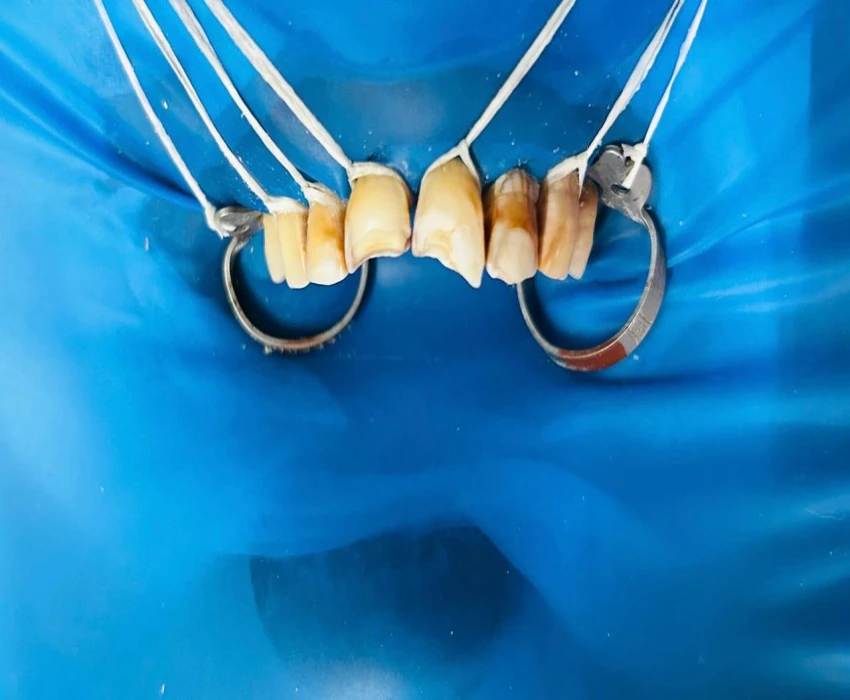

Composite resin restorations have become an integral part of contemporary restorative dentistry and can be called “star of minimal invasion” due to its conservative concepts. The direct composite veneering allows restoring the tooth in a natural way and preservation of sound tooth structure when compared to indirect restorations.